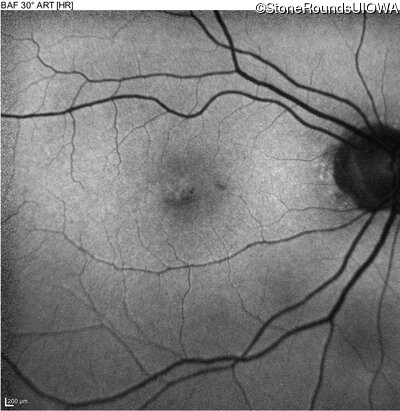

This 70 year old woman first noticed some reduction in visual acuity in both eyes at age 45. Her visual acuity had been previously normal.

The clinical features favoring the diagnosis of RP1L1-associated occult macular dystrophy include: reduced acuity with a near-normal ophthalmoscopic appearance, a history of normal acuity in childhood; and, a "moth-eaten" appearance of the macular ellipsoid zone on OCT.